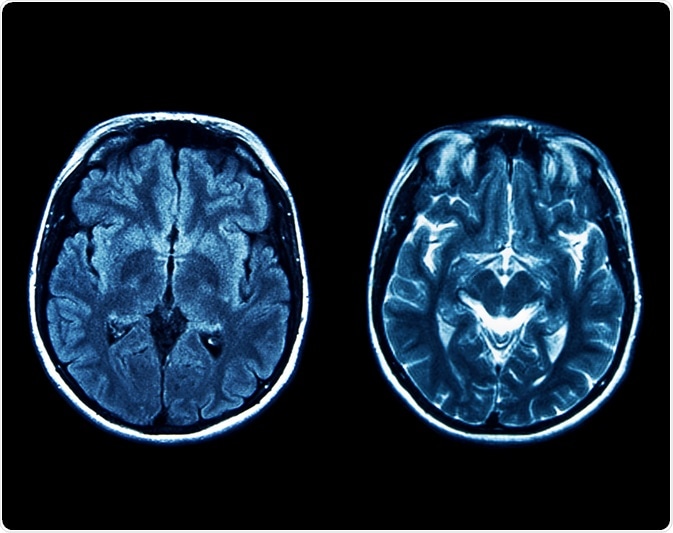

Joubert syndrome is an autosomal recessive neurodevelopmental disorder that is characterized by a brain abnormality called the “molar tooth sign.” The molar tooth sign, which is visible on brain imaging studies like magnetic resonance imaging (MRI), results from the abnormal development of regions in the cerebellar vermis and the brainstem. These specific brain abnormalities resemble the cross-section of a molar tooth when seen on an MRI, hence the name.

Image Credit: gmstockstudio / Shutterstock.com